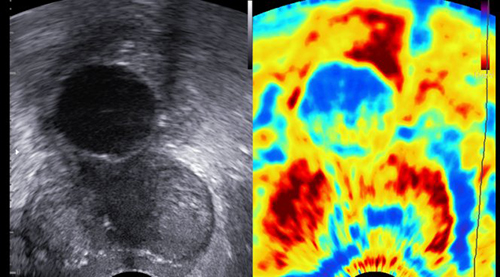

Метод существенно улучшает качество результатов ультразвукового исследования. Важной целью ультразвукового обследования щитовидной железы является определение природы опухолей - являются ли они доброкачественными или злокачественными. От этого зависит выбор дальнейшей тактики врача. Существенно повысить качество обследования позволяет эластография - свидетельствуют результаты исследования ученых из университетской больницы Франкфурта-на-Майне.

Ученые ставили своей задачей определить точность метода в различении узлов щитовидной железы. В исследовании на базе семи медучреждений Германии приняли участие 602 пациента с 657 узлами в щитовидной железе, из них 90 – злокачественных. Сочетание УЗИ и эластографии позволяет достигать 90% точности в определении доброкачественных новообразований. Это позволяет существенно сократить число диагностических операций - утверждает профессор Йорг Боюнга из университетской больницы Франкфурта-на-Майне.

Злокачественные опухоли менее эластичны, чем доброкачественные, поэтому эластография позволяет точнее определять, о каком виде опухолевой ткани идет речь. Тем самым пациенты с безопасными новообразованиями освобождаются от дальнейших обследований, например, инвазивной пункции.